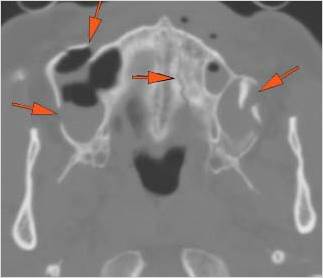

There is bony injury or displacement of the body, angle, ramus, parasymphyseal region, alveolar ridge, and condylar and coronoid process of the mandible. [In case of fracture, describe complexity and displacement].

There is entrapment of the muscles of mastication or other soft tissues by fractures of the coronoid process and/or zygomatic arch.

There is entrapment of the muscles of mastication by fractures of the coronoid process and/or zygomatic arch.